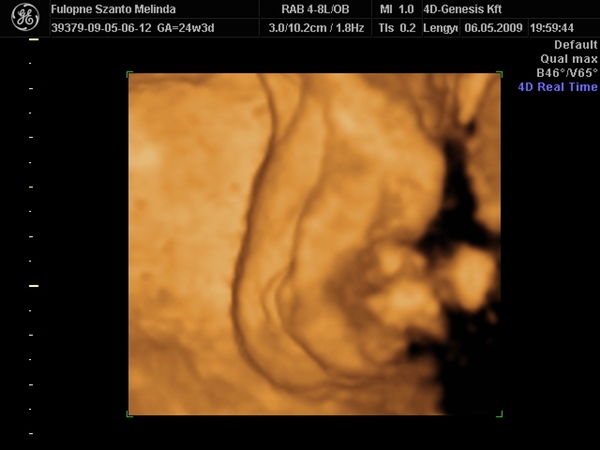

Tegnap az sztk-ban összefutottam Melindával,mondta ma mennek 4D-re Pestre.Melinda,majd írj,hogy mi volt! :lol: :wink:

Nemsoká indulunk a 4 d-re,hát nem igérem,hogy még ma ideérek,de írok Sziszinek sms-t.

Megjöttünk!!!Azért nem dobtam sms-t,mert tudtam,hogy még gép elé ülök ma!!!

Kislány,100%---holnap rakok képet,mindent,csak most áááágyat!!! :lol:

Na rakok képet,Budán voltunk a 4d genesis,de megmutatom,van honlapja.... Kép Kép Kép Kép Kép

Szóval!Nagyon csodálatos volt látni (nekem újra) a picúrt! :lol:

Mint ahogy kiderült,nem is olyan picúr!Ma vagyok 15 hét 2 napos,a bab méretei meg 16 hetesnek felel meg.Persze tudom,ez még változhat.Szegénykém olyan furi pózt vett fel,de hát ha neki úgy kényelmes,legyen úgy! :lol: :lol: :lol: :wink: Úgy képzeljétek el,mint a fordított C betű.Lent van a feje,felfelé áll a törzse és balra fordulva a lábai.Nem tudom elég érthető volt e így,de sajna jobban nem tudom elmagyarázni.

A méretei:

BPD:3,6 cm

OFD:4,4 cm

HC:12,85 cm

FL:1,96 cm

AC:9,69 cm

CRL:9,83 cm

A szivecskéje is nagyon vert,olyan jó volt hallani,láttam párom is belekönnyzett! :shock: :lol:

És végül úgy néz ki,90 % hogy KISFIÚ!!!!!!